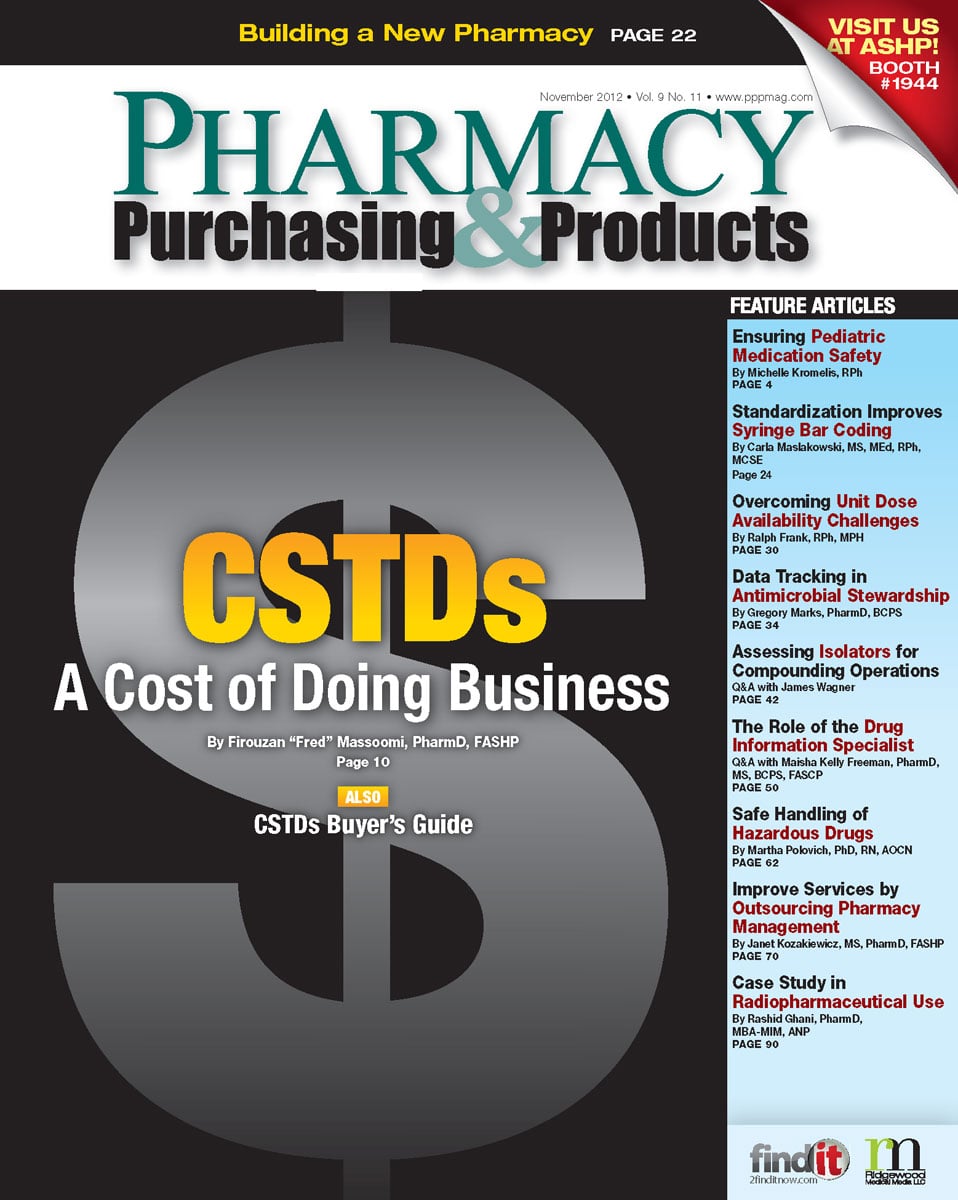

November 2012

Volume 9,

Number 11

Articles: 16